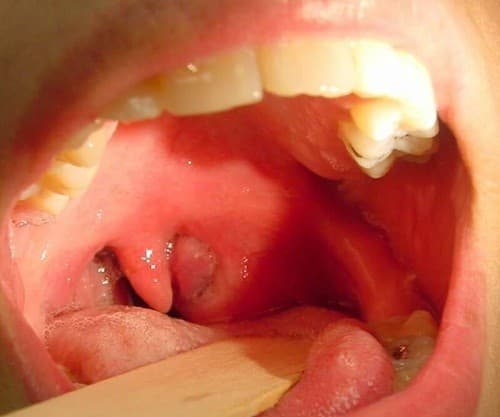

Khi bạn bị đau họng, ho, sốt hoặc thấy có mủ quanh amidan thì có thể đó là những triệu chứng viêm amidan hốc mủ. Nhiều người do thiếu kiến thức về căn bệnh này nên không phát hiện sớm. Viêm amidan hốc mủ nếu không được điều trị kịp thời có thể gây biến […]

Viêm amidan mạn tính là hiện tượng viêm thường xuyên, bệnh tái đi tái lại nhiều lần. Tuỳ theo mức độ viêm nhiễm và phản ứng của cơ thể, amidan có thể (quá phát) thường gặp ở trẻ em hay người trẻ tuổi, hoặc amiđan có thể nhỏ lại (xơ chìm). Tỷ lệ viêm amidan […]

Viêm amidan là bệnh lý thường gặp ở cả người lớn và trẻ em. Bệnh tiến triển thành từng đợt, có thể tự khỏi, có thể đưa đến biến chứng tại chỗ hoặc toàn thân, rất nguy hiểm. Thông qua những biểu hiện của viêm amidan dưới đây sẽ giúp độc giả phát hiện sớm […]

Thông thường, amidan bắt đầu hoạt động lúc bạn 3 tuổi, nó phát triển ở tuổi thiếu nhi và teo dần ở tuổi dậy thì. Khi nhiễm vi khuẩn hoặc virus, amidan sẽ bị viêm nhiễm, sưng to, tấy đỏ. Tình trạng này kéo dài sẽ gây khó khăn trong ăn uống, làm người bệnh […]